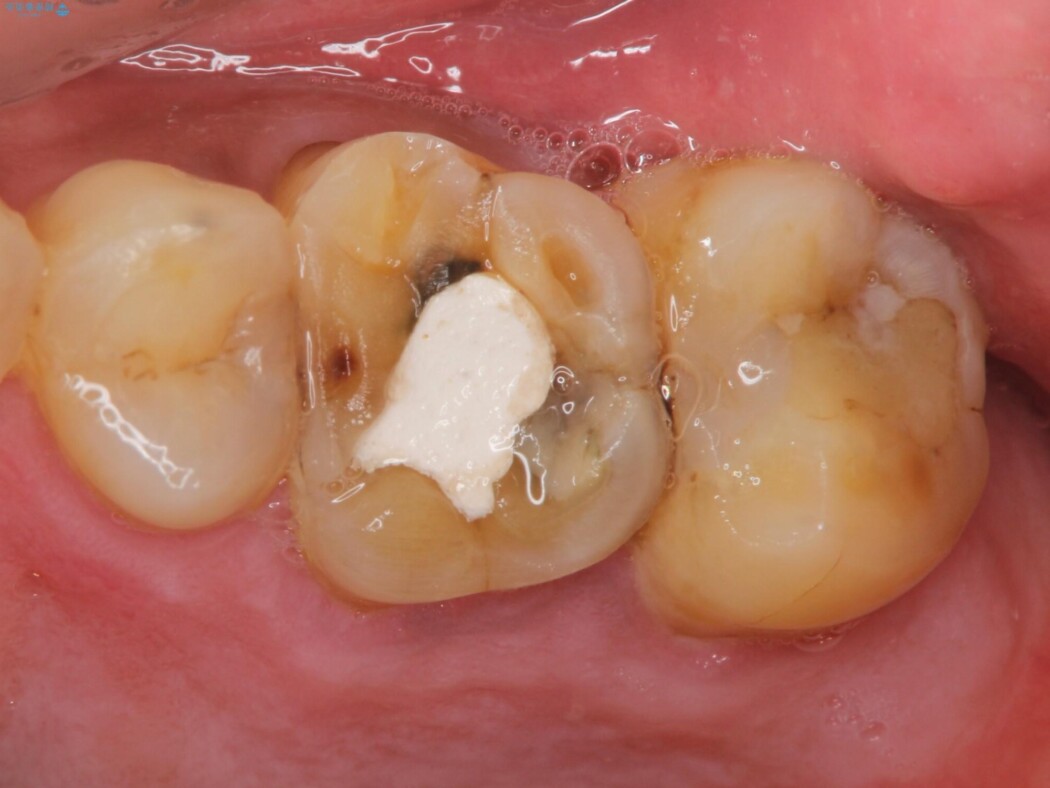

検査をしたところ不可逆性歯髄炎と認めました。

虫歯を取り除いてみると深いクラックラインが明確に確認できたため、全て除去して抜髄処置を行う方針としました。